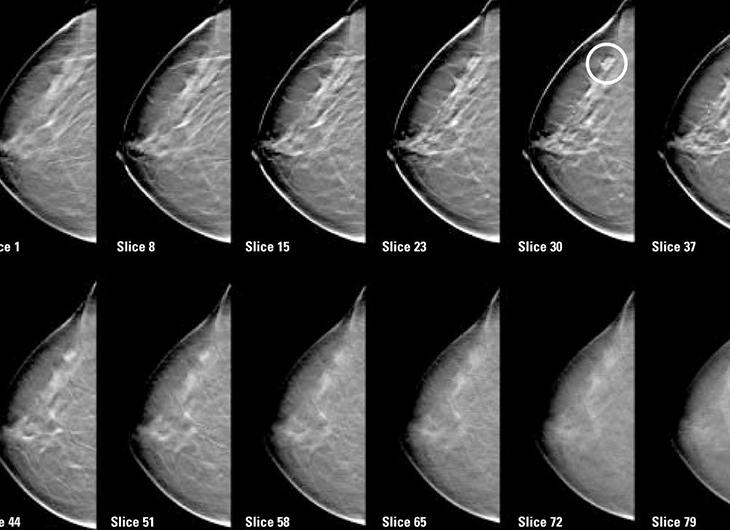

Стандартная маммография заключается в том, что выполняется по два снимка в разных проекциях обеих молочных желез. Даже если у Вас имеется опухоль только в одной железе, делается маммография обеих желез. Это позволяет, во-первых, сравнить обе молочных железы, что облегчает распознавание изменений в их ткани, и, во-вторых, проверить вторую железу на наличие изменений. Если Вам проводилась маммография ранее, то врач сравнит прошлые снимки с настоящими.

Развитие технологии превратило обычное рентгеновское исследование в цифровую маммографию, которая позволяет улучшить визуализацию молочных желез, в частности, для женщин моложе 50 лет, женщин с плотной тканью молочной железы, для женщин в предменопаузе или перименопаузе. Цифровая маммография преобразует обычное ренгеновское изображение молочных желез в электронные, которые могут быть улучшены с помощью компьютерных технологий, могут сохраняться на компьютерах, и даже передаваться в электронном виде для дистанционной консультации. Процедура цифровой маммографии осуществляется так же, как и стандартная маммография. При исследовании также используются рентгеновские лучи, но мощность их значительно ниже.

Как цифровая маммография выполняется.

Стандартная процедура выглядит следующим образом:

Вся процедура исследования занимает 20-30 минут.

Пациентка раздевается до пояса, освобождает грудь.

Исследование проводится сидя, стоя или лежа. Каждая грудь располагается между двух пластин маммографического аппарата и несколько прижимается пластинами (это может вызвать временный дискомфорт и даже боль). Сжатие груди необходимо для уменьшения слоя исследуемой ткани, получения наилучшего изображения и для уменьшения лучевой нагрузки.

Во время снимков потребуется задержать дыхание на несколько секунд. Рентгенолог во время снимка будет находиться за защитным окном. Стандартное исследование подразумевает снимок каждой железы в 2х проекциях – сверху вниз и горизонтально, справа налево.

После этого, пациентке будет предложено подождать в течение короткого времени, пока рентгенолог просмотрит изображения. Возможно потребуется выполнить дополнительные исследования в косых проекциях или прицельные снимки.